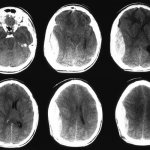

The child’s arms, legs, and chin are trembling—maybe he is cold or has some kind of neurological disease?

Shaking, or tremor, is a physiological phenomenon that occurs in most children in the first 3 months of life.

Tremor appears again due to the immaturity of the nervous system. Trembling usually occurs while crying or after some kind of exertion (for example, after swimming), but sometimes it begins quite suddenly, perhaps even at rest. When a child has tremors, the chin and lower lip usually tremble, and the arms and legs may also tremble.

Tremor can be symmetrical (both arms tremble) and asymmetrical, when different parts of the body tremble separately (for example, the chin and arms or one arm and one leg tremble at the same time).

As soon as parents notice that the baby has a tremor (and it may not appear immediately after birth, but even a month later), they are very worried. However, as we have already said, this is normal in young children. Nevertheless, you need to pay attention to the following points: physiological tremor does not last long - only a few seconds; if the tremor intensifies, the episodes become more frequent and longer, you need to show the baby to a neurologist.